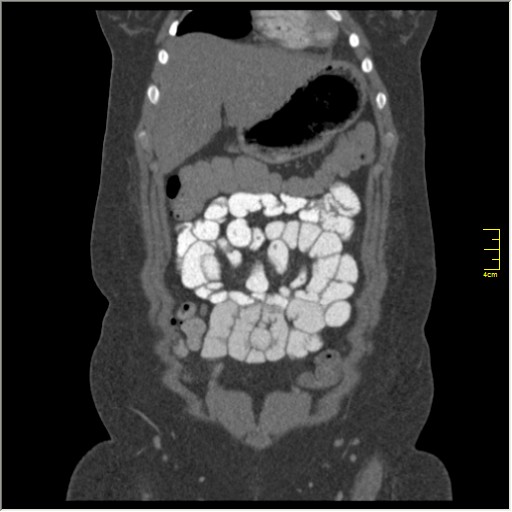

КТ энтерография

Демонстрационные изображение, оцените возможности метода! Толщина среза реконструкции 0.5-1 мм.